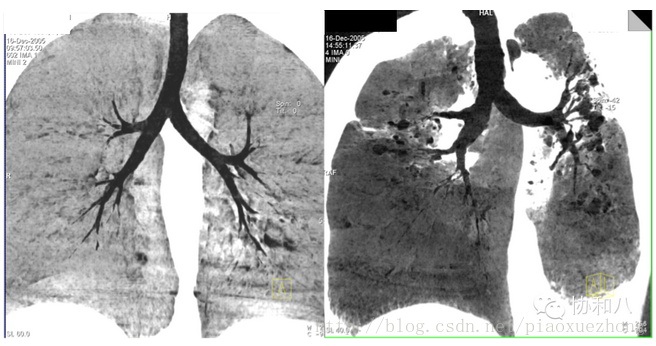

最大密度投影(MIP)

最大密度投影是将一定厚度(即CT层厚)中最大CT值的体素投影到背景平面上,以显示所有或部分的强化密度高的血管和/或器官,简单原理和图像是酱紫的:

由于这种方法显示的是一定层厚图像中CT值最高的体素,所以变化层厚会对图像产生影响:

层厚5mm 层厚15mm

肿么样,是不是觉得层厚5mm的MIP图像上门脉有狭窄,而层厚15mm的MIP图像上门脉是正常的?

由于MIP常用来显示血管的走行(问我为啥常用来显示血管?因为增强CT上血管比周围组织器官亮啊~),所以层厚的选择很重要,既不能太薄(血管的部分管腔可能在层厚以外),又不能太厚(周围组织器官有干扰),这是很考验放射科大夫的技术和临床经验的。

下面给大家比较下MPR和MIP的图像:

可以看到,MIP图像中的血管连续性更好。

MIP这种技术有个双胞胎——最小密度投影(minIP),和MIP正好相反,反映的是一定层厚图像中CT值最低的体素,所以常用来显示胆道、气道等组织结构。